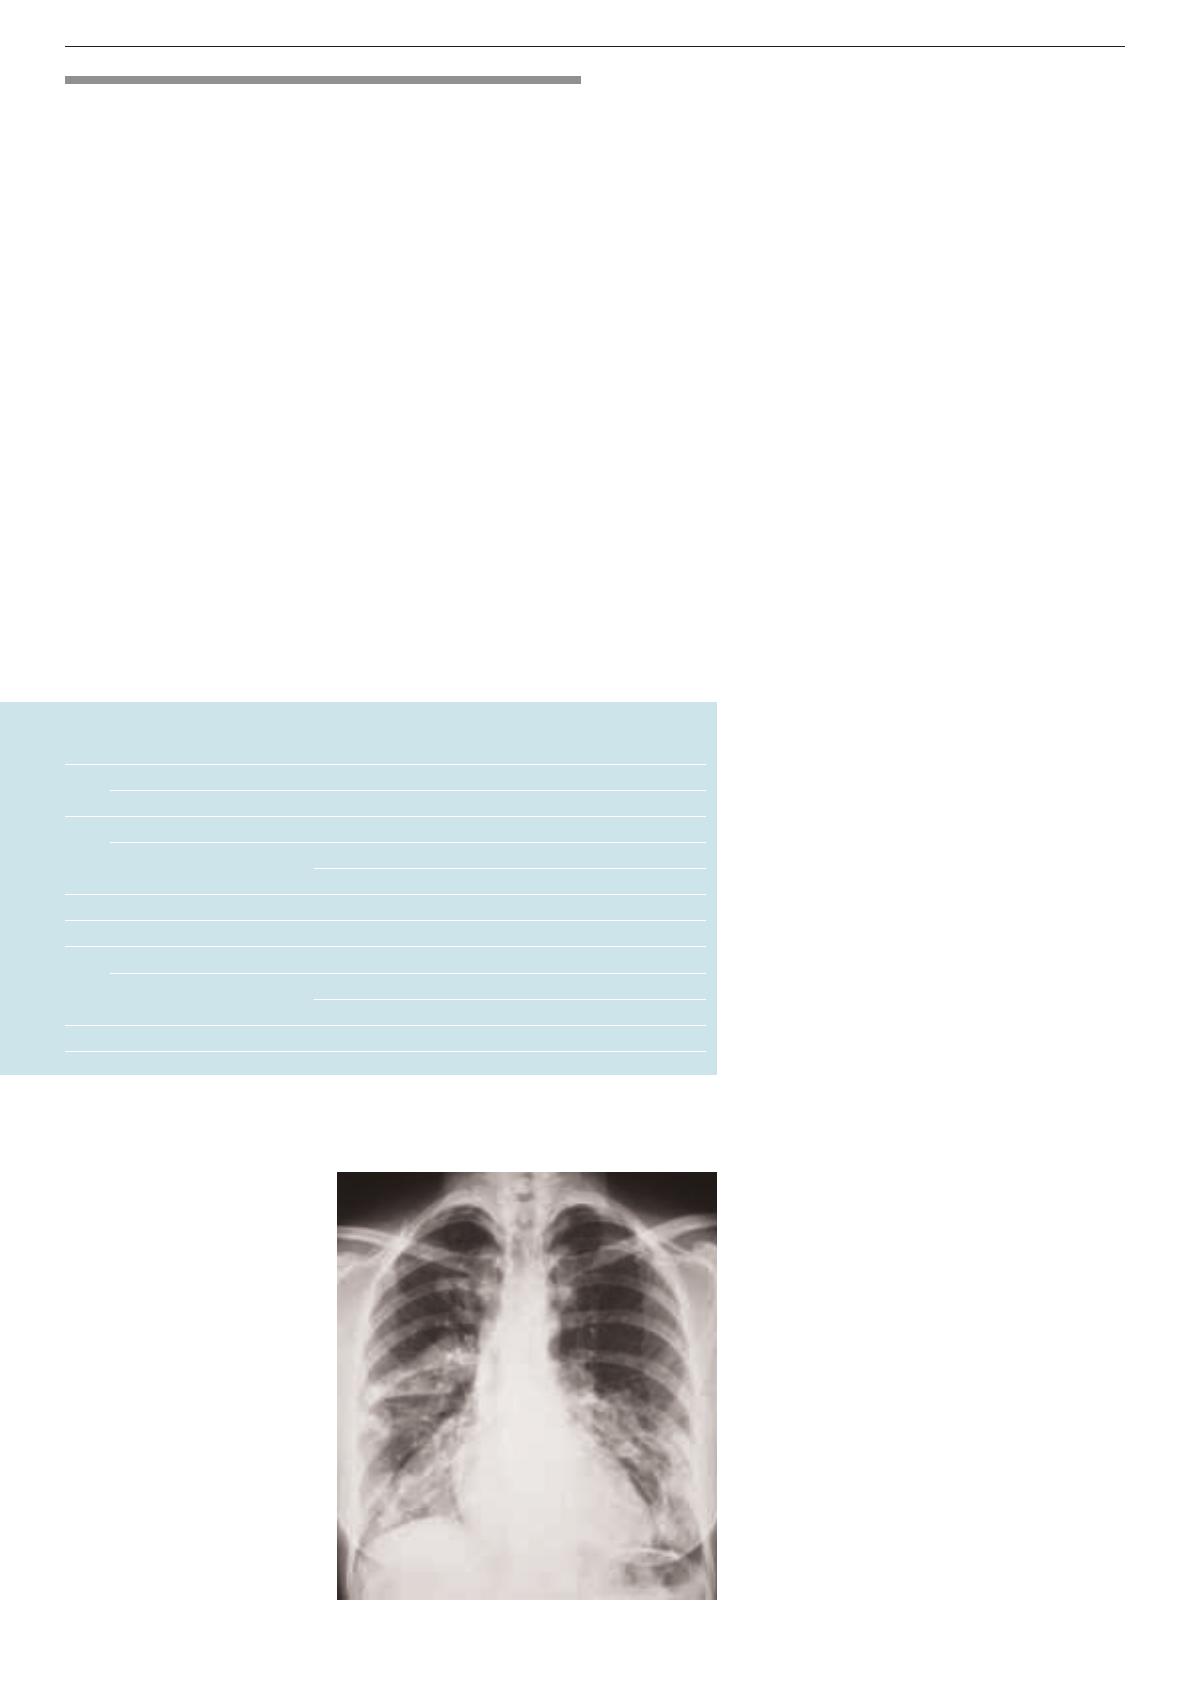

les éléments cliniques, de laboratoire et radio-

logiques (figure 1) ne permettent pas de faire la

Pneumonie communautaire

distinction entre pneumonies à pathogènes

classiques ou «atypiques».

Figure 1.

Patiente de 27 ans ayant

une pneumonie lobaire bilatérale

étendue, une leucocytose à

19000/µl, une CRP à 180 mg/l et

une pneumonie à mycoplasmes

confirmée par réaction en chaîne

de polymérases.